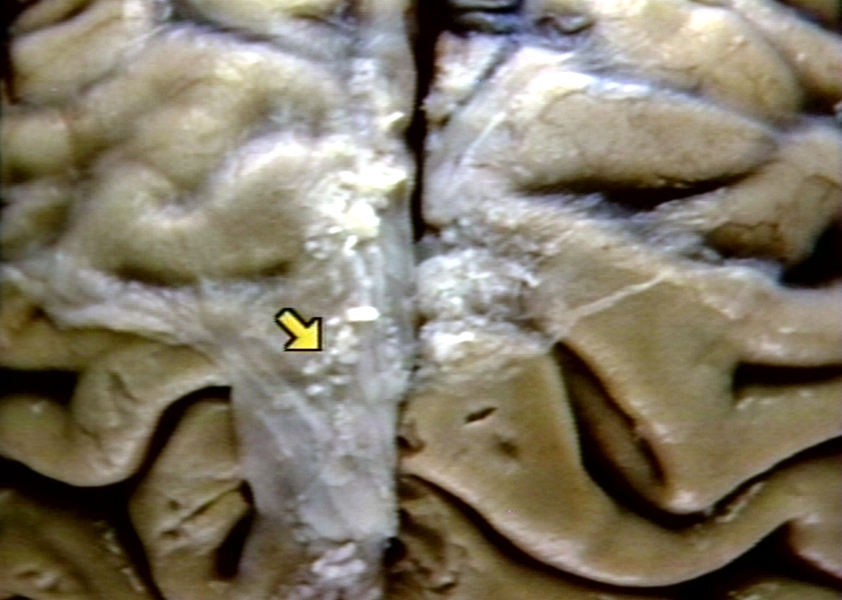

GROSS: NERVOUS: BRAIN: ARACHNOID GRANULATIONS; INTERHEMISPHERIC FISSURE